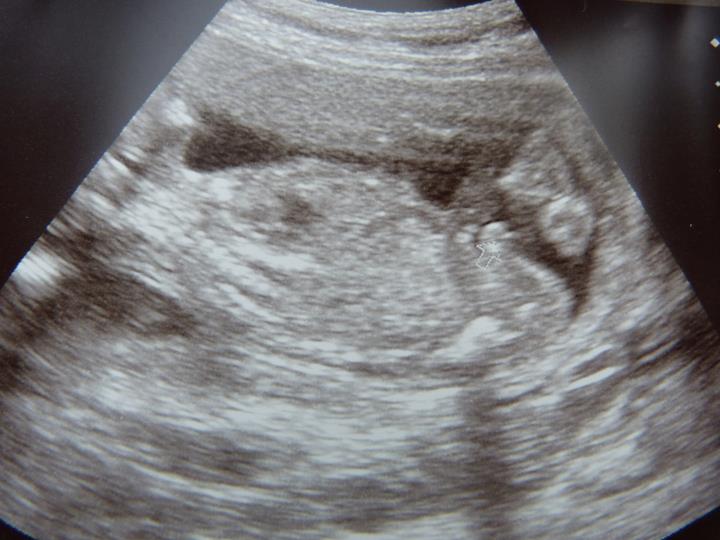

Ultrasound Obstet Gynecol 2011; DOI: 10.1002/uog.7760 Sonographic estimation of fetal head circumference: how accurate are we? N. MELAMED, Y. YOGEV, D. DANON, R. MASHIACH, 0.6–0.9) and male fetal gender (OR, 0.8; 95% CI, 0.6–0.9) were associated with decreased sonographic ... View This Document

Re: How Accurate Is A gender ultrasound At 16 Weeks? - YouTube

97% Accurate Gender Prediction | Rainbow Baby - YouTube